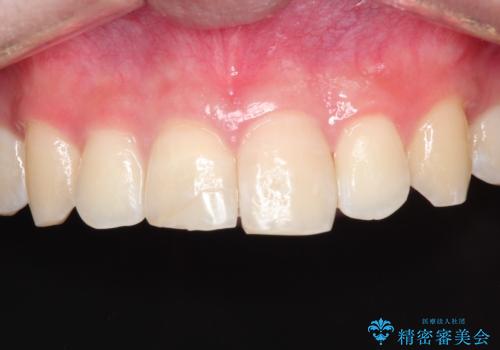

【ホワイトニング】右上前歯の歯茎の辺りが暗いのが気になる。

- 右上1番の色が暗いのを主訴に来院されました。

治療手順としましては、マイクロスコープ(歯科用顕微鏡)を使用し、元々入っていた詰め物のCR(プラスチック)を除去します。その後、歯の中に薬剤を入れ、蓋をします。2週間後に来院して頂き、白くなっているかを確認します。ご本人がご満足頂く白さになるまで、これを3~4回繰り返します。今回は1回で患者様がご満足されたので治療を終了しています。